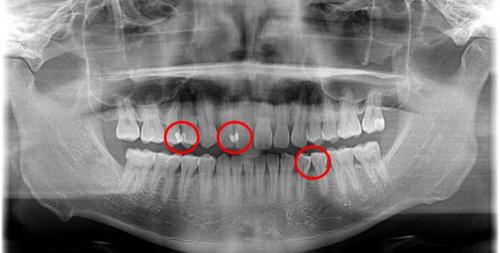

对于牙列拥挤不齐的一些患者来说,如果牙缝清洁工作不到位,邻面龋就很容易发生。

上图一位患者的牙片,很明显因为牙齿拥挤不齐,其中仍有食物嵌塞残留,也就是在牙齿邻接面。这种如果长期嵌塞无法清洁,就会导致牙龈和牙槽骨的炎症、退缩。